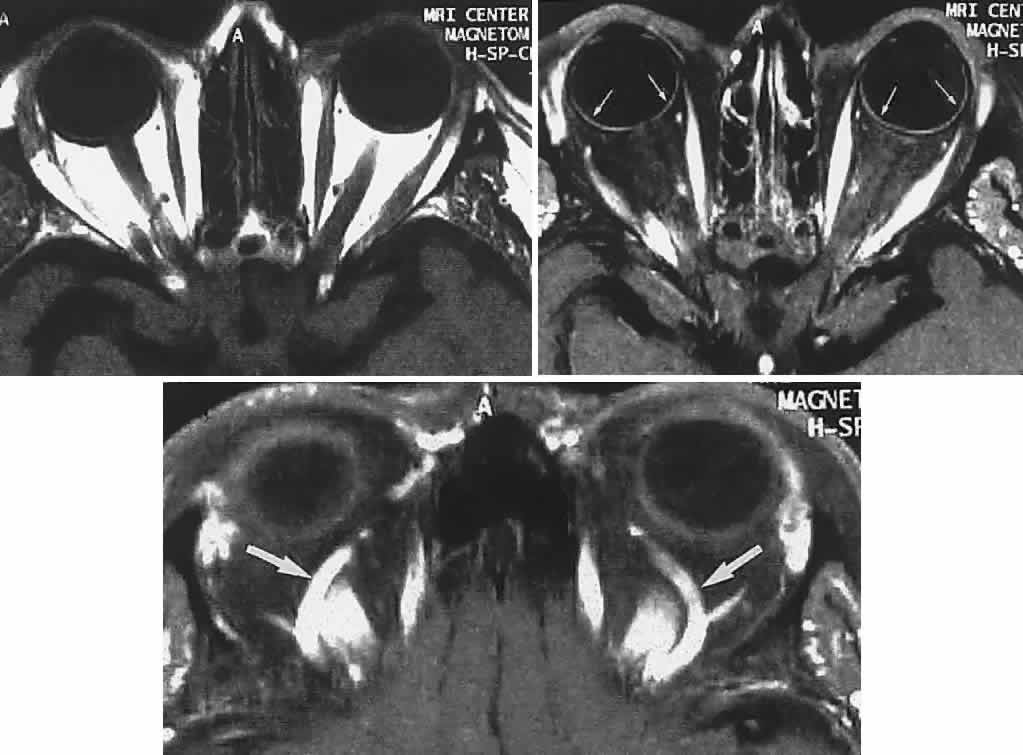

Now almost universally available, MRI is the preferable technique for imaging the soft tissue contents of the orbit, high-resolution 3-mm and thinner sections being available, as well as gadolinium contrast enhancement (Figs. 19, 20, and 21).

Fig. 19. MRI of orbits, axial sections. Top. T1-weighted: orbital fat is white (hyperintense), muscles are dark. Middle. Fat saturation with gadolinium through midorbit: orbital fat signal suppressed (dark), accentuates hyperintense muscles; note also choroid (small arrows). Bottom. Fat-saturation technique through superior aspect of orbit; note superior ophthalmic veins (arrows).

Fig. 20. MRI of orbits, coronal sections. Fat suppression. Top. Midorbit. Middle. Orbital apex. Bottom. T2-weighted. Arrows indicate optic nerve; note ring of CSF (bottom).

Fig. 21. Young patient had slowly evolving unilateral proptosis. Left. Enhanced CT scan shows laterally placed homogeneous mass. Right. MRI with contact coil shows mass well separated from optic nerve and splaying lateral rectus (arrows) on medial surface of lesion; tumor was a fibrous histiocytoma.